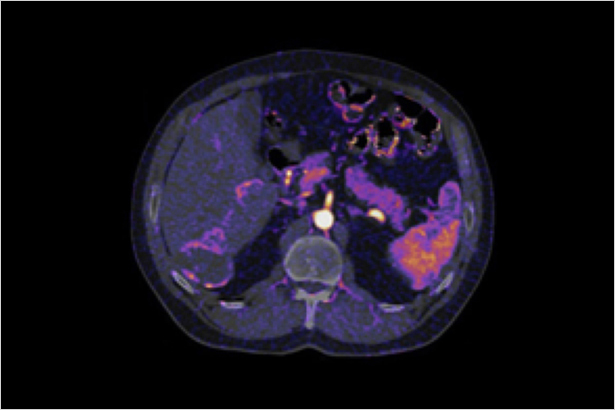

秉承佳能醫療超高端640層CT的AI同步軌道掃描技術與柔性掃描與彩色成像技術,在不增加掃描代價和患者輻射劑量代價的前提下,利用平掃和增強數據進行柔性的器官配準,0鍵式地得到彩色碘圖等有價值的診斷信息,更敏感地發現病灶和淹沒在器官背景的微小血供變化。

在柔性彩色體部成像下,淹沒在器官背景中的強化,可以在彩色碘圖下,顯著地表達出來。